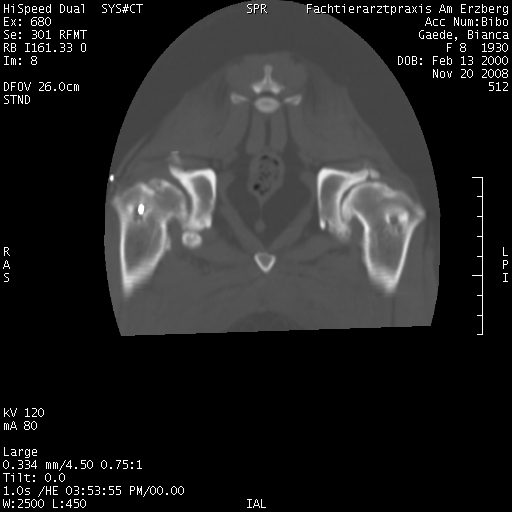

Nachstehend die Aufnahmen der im November gemachten CT, dort kann man sehen, wie krass die Hüfte entartet ist und wieviel Arthrosen sich gebildet haben, für mich waren es die totalen Horrorbilder, vor allem, wenn ich an die ersten Röntgenaufnahmen ihrer Hüfte denke, wo mein TA auch die Möglichkeit des Einschlafens erwähnt hat, weil er meinte, daß Bibo mit dieser Hüfte kein Leben ohne Schmerzen führen kann.Externer Inhalt www.fotos-hochladen.netInhalte von externen Seiten werden ohne deine Zustimmung nicht automatisch geladen und angezeigt.Externer Inhalt www.fotos-hochladen.netInhalte von externen Seiten werden ohne deine Zustimmung nicht automatisch geladen und angezeigt.Externer Inhalt www.fotos-hochladen.netInhalte von externen Seiten werden ohne deine Zustimmung nicht automatisch geladen und angezeigt.Externer Inhalt www.fotos-hochladen.netInhalte von externen Seiten werden ohne deine Zustimmung nicht automatisch geladen und angezeigt.Externer Inhalt www.fotos-hochladen.netInhalte von externen Seiten werden ohne deine Zustimmung nicht automatisch geladen und angezeigt.Externer Inhalt www.fotos-hochladen.netInhalte von externen Seiten werden ohne deine Zustimmung nicht automatisch geladen und angezeigt.Externer Inhalt www.fotos-hochladen.netInhalte von externen Seiten werden ohne deine Zustimmung nicht automatisch geladen und angezeigt.Externer Inhalt www.fotos-hochladen.netInhalte von externen Seiten werden ohne deine Zustimmung nicht automatisch geladen und angezeigt.Externer Inhalt www.fotos-hochladen.netInhalte von externen Seiten werden ohne deine Zustimmung nicht automatisch geladen und angezeigt.Bibo ist inzwischen 8 Jahre alt und wir hatten wirklich schlimme Zeiten, weil sie auch schwere Spondy (wie man auch auf den Bildern erkennen kann) und inzwischen auch Cauda Equina hat (macht ihr aber zum Glück keine Probleme). Durch die Spondy habe ich im September/Oktober 2007 gedacht, daß ich sie einschläfern lassen muss, weil ich ihre Schmerzen nicht mehr ertragen konnte. Aber ich hatte sehr viel Glück, durch das Forum vor allem und konnte Bibo im November 2007 eine Goldakku machen lassen.

Hier die CT-Bilder: